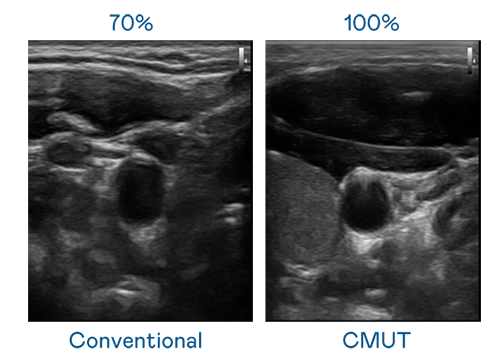

CMUT 技术是一种用电容式微机电元件来产生超音波讯号的技术。与传统 PZT 压电式技术相比,CMUT 频宽增加 30%,更宽频的超音波讯号让影像解析度大幅提升,是实现高影像品质医疗超音波扫描、促进精准医疗发展的关键技术。

大频宽带来超清晰影像

超音波影像的解析度高低,首先取决于探头能发出的讯号频宽。304am永利 CMUT 可提供高清晰的超音波讯号,提供高频宽、高灵敏度、影像纹理细节更高的超音波影像,协助医护人员缩短影像判读时间及利用精准的医疗影像进行诊断。